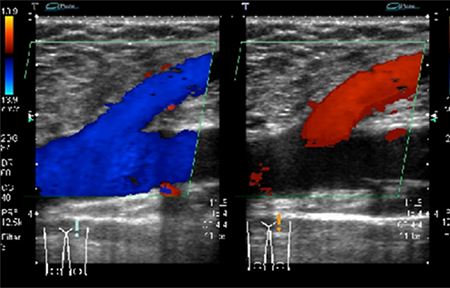

当院では、超音波(エコー)検査を中心に診断を行っています。エコー検査は無痛で、妊婦健診でも用いられる安全な検査方法です。

エコー検査

エコー検査の画像